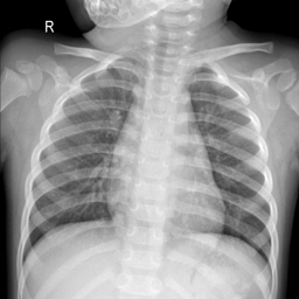

Samples of the dataset are depicted in Figure 3.

The dataset is arbitrarily partitioned among each client (). , and then the prediction performance results in the encrypted-domain are compared with the results of the plain-domain.